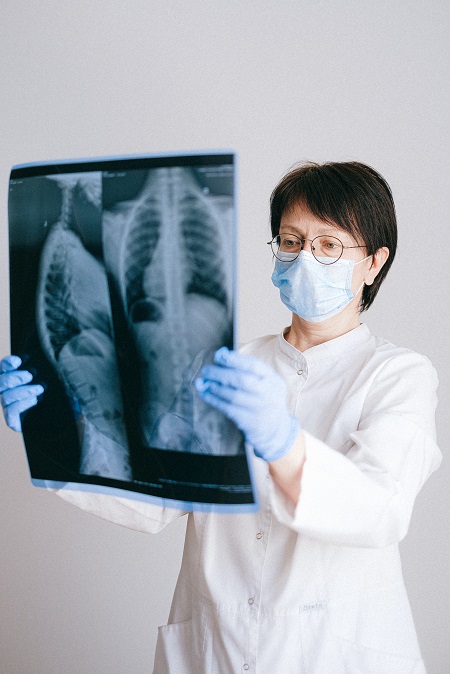

Excellent Infrastructure

We have state of art Infrastructure with technically advanced equipment for diagnosis and treatment.

With the support and continuous improvement on our facility, we deliver best services to all patients.